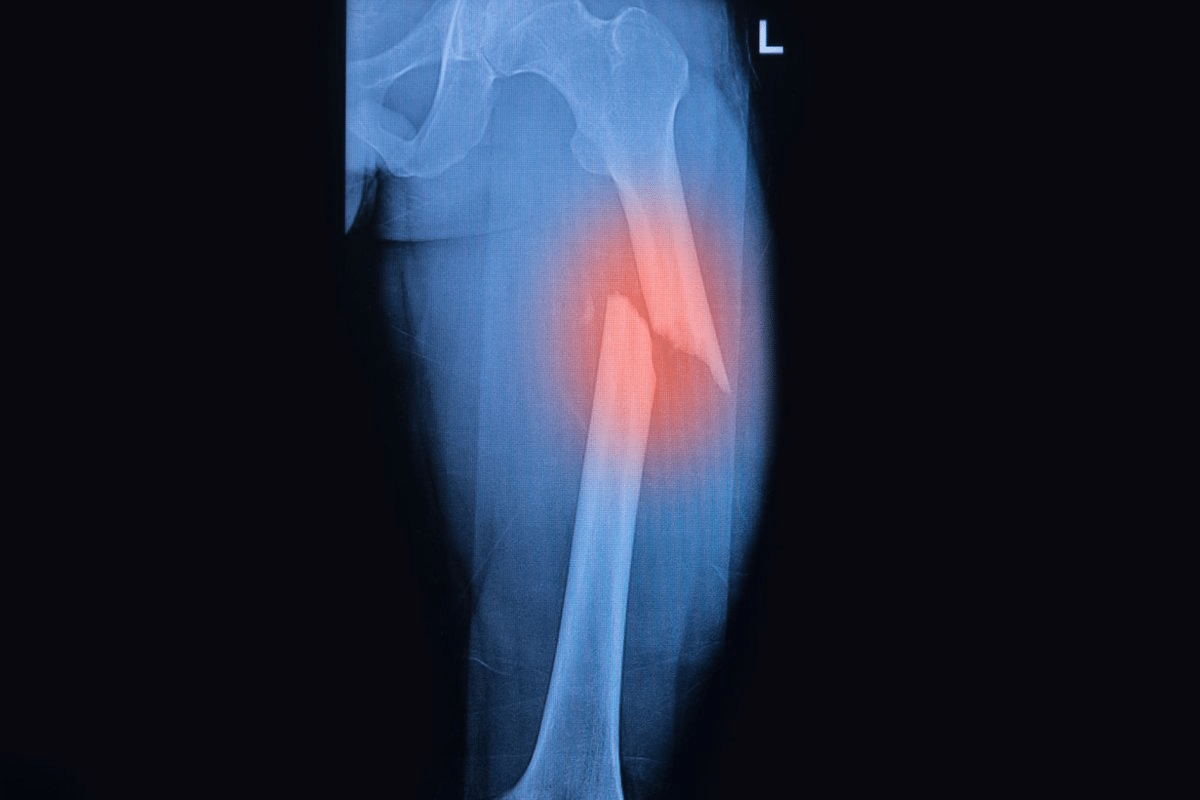

Medication for Fracture: Best Safe Care

Choosing medication for fracture pain management is vital. Learn about the safest and most effective drug options for healing and comfort. Choosing the right treatment for older veterans is complex. It involves looking at each person’s health and what they hope to achieve. Managing fracture risk in this group needs careful thought about the good and bad sides of different treatments.

Fractures are a big health problem for older veterans. They affect their quality of life and overall health. It’s clear that fractures need careful care and management.

Fractures are a big issue for older veterans. They cause a lot of health problems and even death. Factors like osteoporosis, less mobility, and other health issues contribute to this.

The effects of fractures on older veterans’ lives are huge. It’s not just physical health. It also affects their mental and social well-being. Veterans with fractures may feel a lot of pain, lose their independence, and have trouble moving.